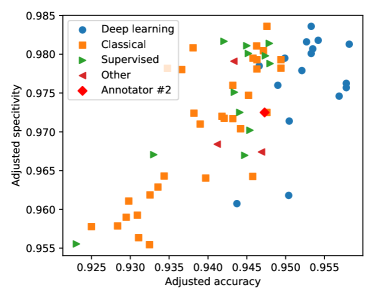

In Figure 6 we have plotted the distribution of algorithms and evaluation methodologies in the adjusted accuracy-specificity plane. The plot shows that after eliminating the bias, the algorithms evaluated with all pixels have lower accuracy and specificity scores than those evaluated with the FoV mask. The independent two-sample t-test shows that the difference is statistically significant with a p-value of . The reason for this surprising phenomenon is that using all pixels to evaluate less effective techniques results in performance scores comparable to or even higher than those of more effective techniques evaluated under the FoV mask, and this brings publicity to less effective approaches.

Finally, we compare the performances of the methods by their operating principles. We have introduced 4 categories: deep learning, classical (thresholding, filtering, morphology, region growing), supervised (feature extraction and supervised machine learning, but not deep learning), and others (dominantly graph-cut based segmentation techniques). The results presented in Figure 6 show that deep learning techniques increase the accuracy by almost 1% compared to the best performing classical and supervised techniques.